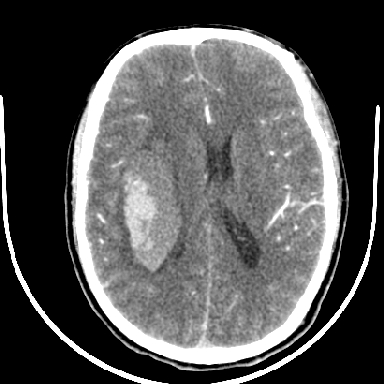

标题: CT6056:脑出血(血管畸形?) [打印本页]

标题: CT6056:脑出血(血管畸形?)

m 40突发头痛左侧偏瘫3小时

考虑高血压性脑出血,依据:

1是高血压性脑出血的好发部位,形态呈肾形,是高血压性脑出血的常见形状

2增强时占位效应加重了,考虑出血还没有停止

3病灶周围水肿不是太厉害,一般肿瘤出血水肿多非常明显

4病灶周围的‘软组织’影没有明显的强化

5至于脑血管畸形引起的出血,暂时没有看到明显的畸形血管影,也不太支持

支持右侧基底节脑出血

右侧基底节区脑出血.

支持右侧基底节区(主要为外囊区)原发性脑出血。

支持右侧基底节区(主要为外囊区)原发性脑出血

另附部分资料:“血液溢出血管外形成血肿,其内含有大量血红蛋白、血浆白蛋白,球蛋白,因这些蛋白对x线的吸收系数高于脑质,故ct呈现高密度阴影,ct值达40~90h,最初高密度灶呈非均匀一致性,中心密度更高,新鲜出血灶边缘不清。基底节区血肿多为“肾”型,内侧凹陷,外侧膨隆,因外侧裂阻力较小,故向外凸,其它部位血肿多呈尖圆形或不规则形”

术中抽出40ml陈旧血液,血肿底部似见一条索血管影